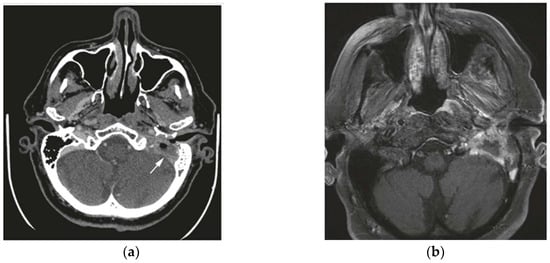

Figure 2. (a) Axial CT and (b) Axial MRI: Tissue occupies the acoustic meatus with the expansion of the auricular and condylar base without apparent erosive phenomena. Diagnosis of keratinizing squamous cell carcinoma and figure-free lymph node referable to metastasis. Legend: SCC (squamous cell carcinoma), EAC (external auditory canal), CT (computed tomography), and MRI (magnetic resonance imaging).

The preoperative radiological staging and the final pathological staging correlated in 11 (73%) of the 15 cases. The 73% correlation between radiologic and pathologic staging is remarkable and suggests a moderate level of reliability of the imaging modalities used. However, the discrepancies observed, particularly in cases where radiologic staging underestimated or overestimated pathologic findings, warrant further analysis. Factors such as the resolution limits of imaging techniques, variability in tumor presentation, radiologists’ experience, or ambiguous tumor features (e.g., small erosions or subtle soft tissue involvement) could contribute to these discrepancies. This finding could underscore the need for improving imaging protocols and staging accuracy with grids of observations. Radiological staging underestimated the stage in two cases and overestimated it in two others (Table 3). Table 3 highlights the discrepancies between radiological and pathological staging, illustrating cases where imaging underestimated or overestimated the tumor stage. These differences, seen in both T1–T2 and T3–T4 stages, emphasize the challenges in accurately determining tumor extent solely through imaging and underline the importance of multimodal evaluation to improve diagnostic precision (Figure 1 and Figure 2). Radiological staging correlated more frequently with pathological staging for T3 and T4 tumors compared to T1 and T2 tumors (86% vs. 63%). The Cohen’s Kappa value for evaluating the agreement between radiological and pathological staging was 0.66, indicating substantial agreement. This suggests a significant level of concordance between the two staging methods. Discrepancies may be attributed to the complexity of visualizing tumor extension through imaging or the possibility that some details were not easily identifiable with the imaging techniques. Therefore, a multimodal diagnosis, combining imaging and pathological evaluation, is emphasized to achieve accurate staging of temporal bone SCC.

Three patients with T4 disease diagnosed by CT underwent preoperative contrast-enhanced temporal bone MRI. The MRI results did not alter the preoperative staging but provided additional information on tumor extension into soft tissues. MRI showed dural enhancement in two patients and parotid involvement in one patient, which was not visible on CT. Parotid involvement was suspected in one patient but confirmed in two (18%) of the eleven parotid specimens. Radical neck dissection was performed in six (40%) cases, with two (13%) showing lymphatic spread. In both cases of cervical metastasis, preoperative CT had suggested regional disease.